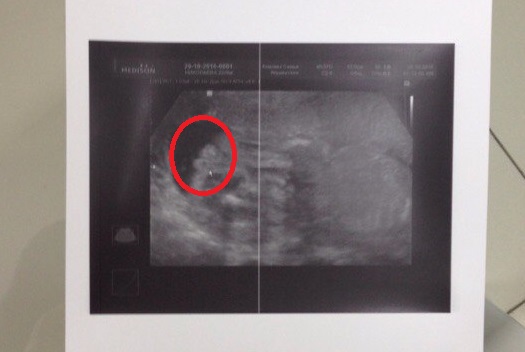

У нас будет ДОЧКА!!!!!!!!!!!!!!!!!!!

сегодня нам 25+2 по М и 23+5 по УЗИ и у нас будет принцесса)))))

ну и фото под кат пирожка))))

Не могла поверить)) да и не видела я экрана(( а тут явно девичья писька)) сомнений у меня нет)